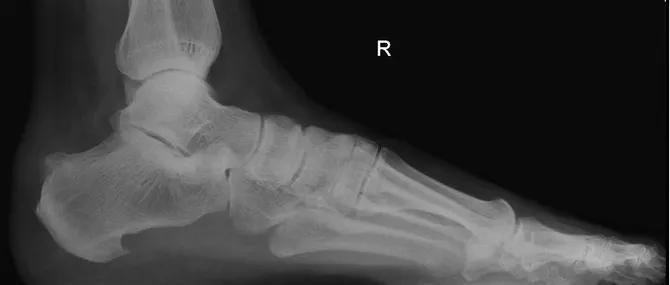

Lateral X-ray with plantar calcaneal Heel Spur.